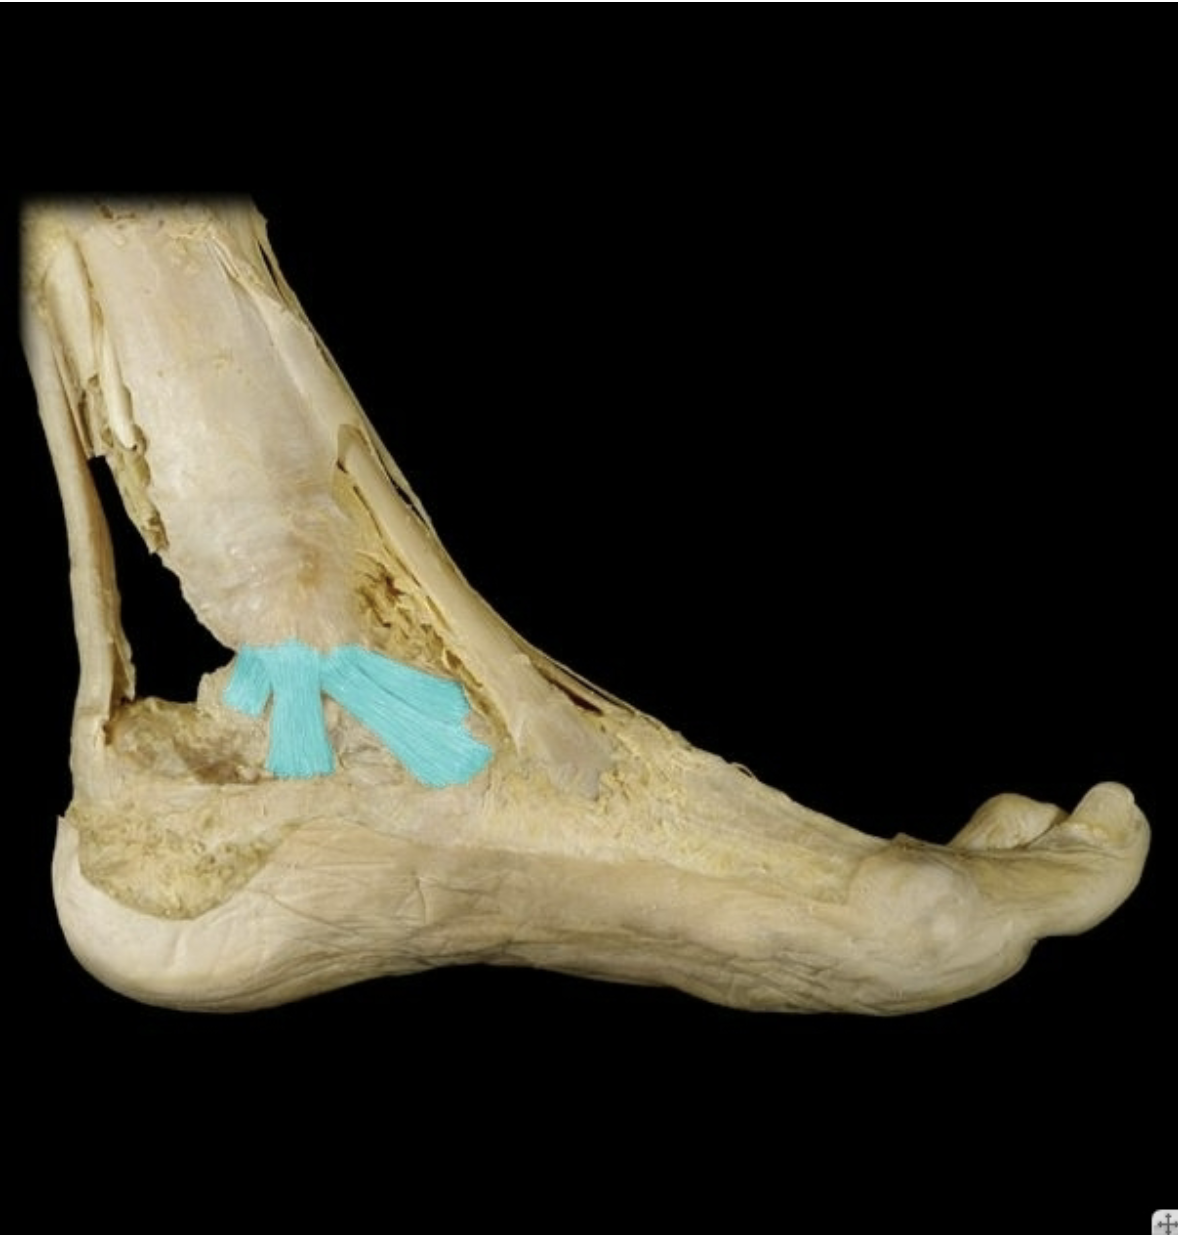

Deltoid (medial) ligament

Lateral ligaments

Posterior talofibular, calcaneofibular, anterior talofibular